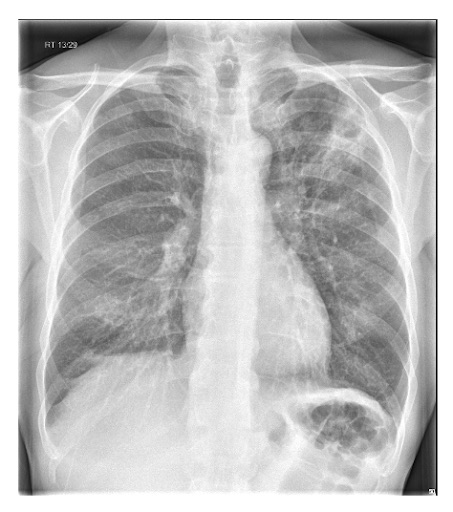

Un nuevo sombreado (consolidación) en la radiografía de tórax confirma el diagnóstico de NAC[1][63][65]

Vuelva a evaluar al paciente si la radiografía de tórax no muestra consolidación.[1][Figure caption and citation for the preceding image starts]: Radiografía de tórax posterior-anterior que muestra consolidación del lóbulo superior derecho en un paciente con neumonía adquirida en la comunidadDurrington HJ, et al. Recent changes in the management of community acquired pneumonia in adults. BMJ 2008;336:1429. [Citation ends].